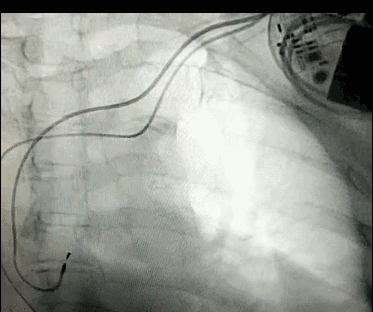

DSA是將造影劑注入需要檢查的血管中,使血管顯露原形,然后通過(guò)系統(tǒng)處理,使血管顯示更加清晰,便于醫(yī)生診斷或進(jìn)行手術(shù)。

數(shù)字減影血管造影術(shù)是醫(yī)學(xué)影象學(xué)中,繼X線(xiàn)CT之后的又一項(xiàng)新技術(shù),也是當(dāng)前醫(yī)學(xué)影象學(xué)中具有突破性的重大進(jìn)展。?